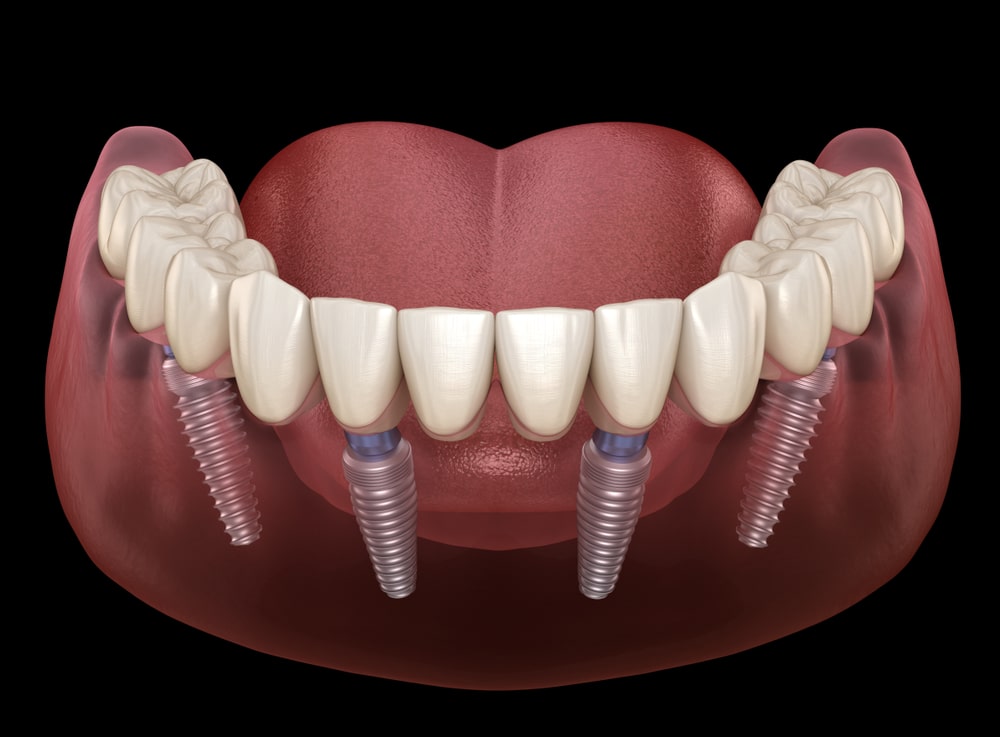

3、植體固定式假牙——All on 4全口重建/all-on-6全口重建

All on 4/all-on-6全口重建係針對骨骼嚴重萎縮、而且需要快速恢復牙齒的人而設計嘅。同傳統植牙相比,最明顯嘅優勢就係速度,若口腔條件允許,最快可以在一日之內完成全口植牙與假牙,唔需要好似傳統植牙一次等待3~6個月以上嘅治療週期。

All on 4/all-on-6全口重建只需要四顆或者六顆植牙,可以大幅縮短手術時間、節省植體費用。

無論是固定式假牙All on 4、All on 6,使用單顎4支/6支植體做為人工牙根,固定於牙床上,藉由拱橋力學設計原理,平均分散植體力量去支撐整排假牙。因此,固定式植牙最接近自然牙的假牙形式,唔單單穩定性高、咬合力佳,亦沒有活動式假牙的異物感。